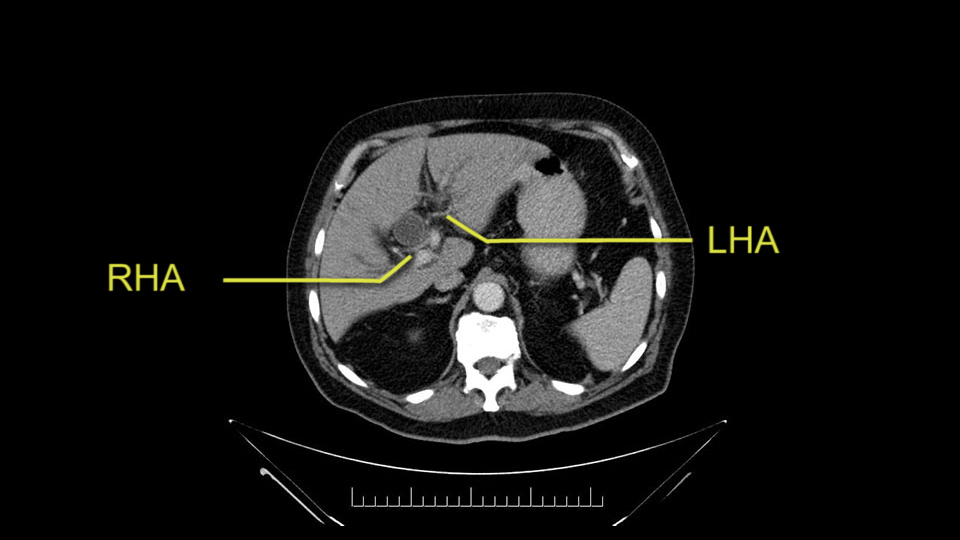

He has normal arterial anatomy: no accessory or replaced right hepatic artery, which is important because sometimes the right hepatic artery can come behind the neck of the pancreas and you have to be careful of that in a Whipple dissection.

Then you look for anomalies. The one you worry about the most doing a Whipple is a replaced or aberrant right hepatic artery coming off the SMA at its origin. So again, find the SMA. You can find it because the renal vein goes through it. Follow it up, up-up-up. Nothing coming off of there that I can see here. Nothing coming off of it, nothing coming off of it and just to confirm it, look at the celiac trfurcation. There’s the celiac, there’s the bifurcation, there's the splenic artery, hepatic artery. Make sure there’s a right, which there is here. The right usually goes under the bile duct: important when you’re going around the bile duct to do a Whipple. A replaced right goes under the portal vein and the bile duct way over here on the right. That’s about it.

The other slowing down moment would be the gastroduodenal artery. Confirming that the gastroduodenal artery is not a dominant artery supplying blood to the liver. Liver failure is something which we don’t want due to altered blood supply to the liver or hampered arterial blood supply to the liver. So I would dissect out the hepatic artery, the left and right branches very clearly. Put a bulldog clamp on the gastroduodenal artery, make sure that the perfusion of the liver is excellent on the right and left side, and then divide the gastroduodenal artery. I would avoid using crushing instruments or crushing clamps on the gastroduodenal artery because they have a tendency to shatter in patients who are old with friable vessels so you have to be careful and tackle it with the help of a 5-0 or a 6-0 prolene sutures. In younger patients, I would just apply clips and move on when it comes to dividing the gastroduodenal artery.

To plan a pancreatoduodenectomy, we start by reviewing the vascular anatomy, especially the origin of the celiac trunk, here, in front of the aorta, looking for any evidence of stenosis. In addition, we look at the origin of the superior mesenteric artery, to look for any branches, and any replaced right hepatic arteries coming from the superior mesenteric artery; which does occur in about 12% of the population.

The second point about the vascular anatomy-, is to again look for right hepatic arteries in the hilum, coming from the superior mesenteric artery by palpating-through the Winslow Hiatus. Usually we will check for a pulse in the posterior aspect of the hepatic hilum, where a right hepatic artery should not usually be found. In this case, the precaution is to avoid an accidental ligation of the right hepatic artery that might jeopardize perfusion of the right lobe, or if there is a completely replaced hepatic artery that can put the liver circulation at risk.

I am a believer in pylorus preservation. And in this case I see no reason why that wouldn't be possible. Mobilize the duodenum, divide the gastroepiploic vessels and divide the duodenum. I try to divide it with a linear stapler about four centimeters from the pylorus to have adequate length for my GI anastomosis. This facilitates exposure of the head neck of the pancreas. I find the gastroduodenal artery. This patient has normal arterial anatomy. Always on every preoperative CT scan I look to see if there is a replaced right hepatic. In this case I did not see one. Regardless of how confident I am I always look carefully for variant anatomy. I always do a clamp test on the GDA before ligation. I doubly ligate the GDA with not just a tie but a suture ligature because of the risk of GDA blowout in patients with a leak.